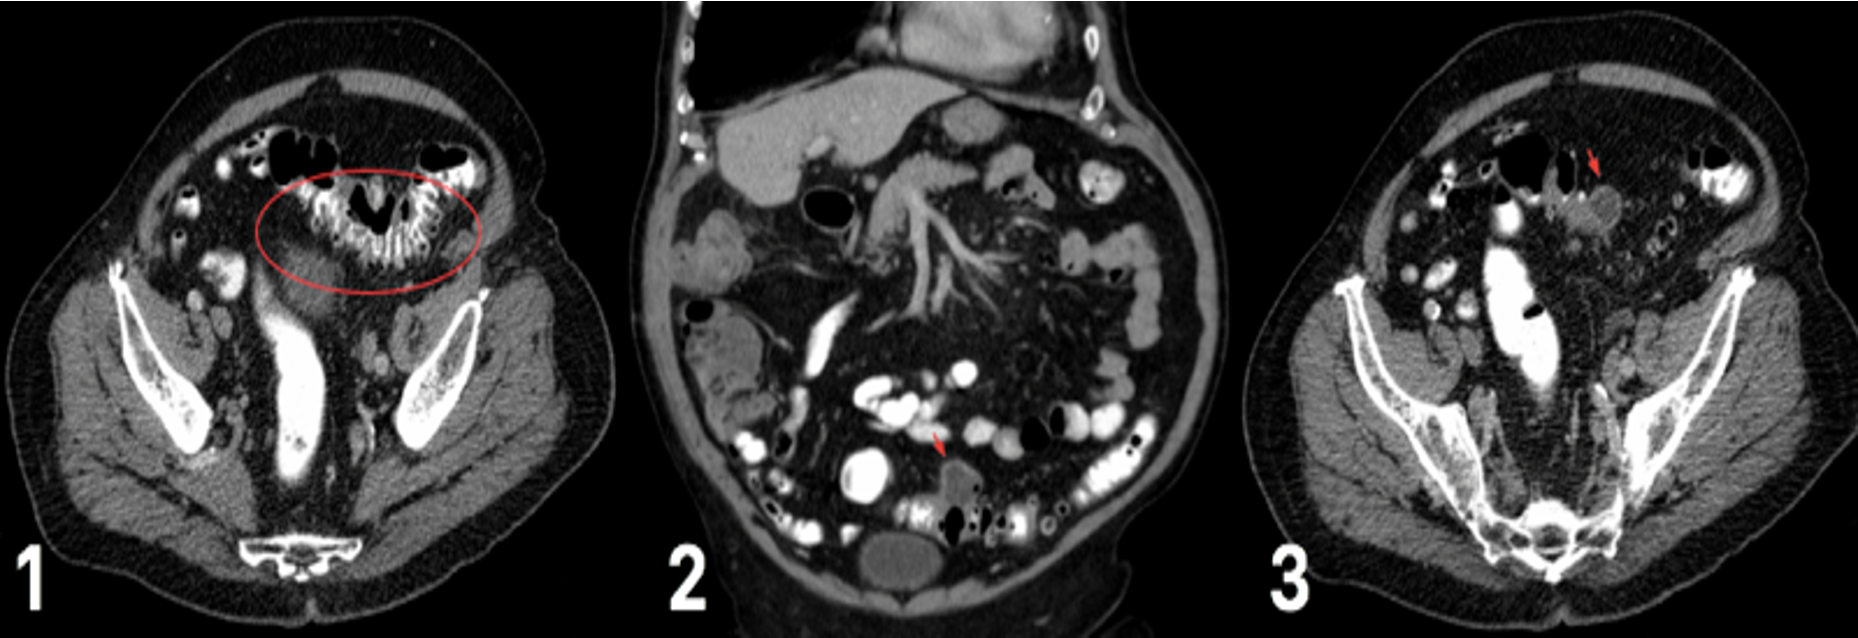

CT scan for varying degrees of diverticular disease (1) diverticulum in the sigmoid colon (2) degree of diverticulitis present (3) abscess formation, secondary to ongoing diverticulitis

Left Iliac Fossa Pain;

Male or female ? D/D Diverticular diseases: Presentation ?